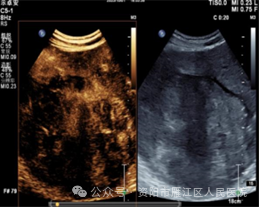

超声造影:肝右叶实性占位性病变,考虑肝细胞Ca可能性大。

为进一步明确肝右叶病变的病理类型,遂行超声引导下肝肿物穿刺活检: